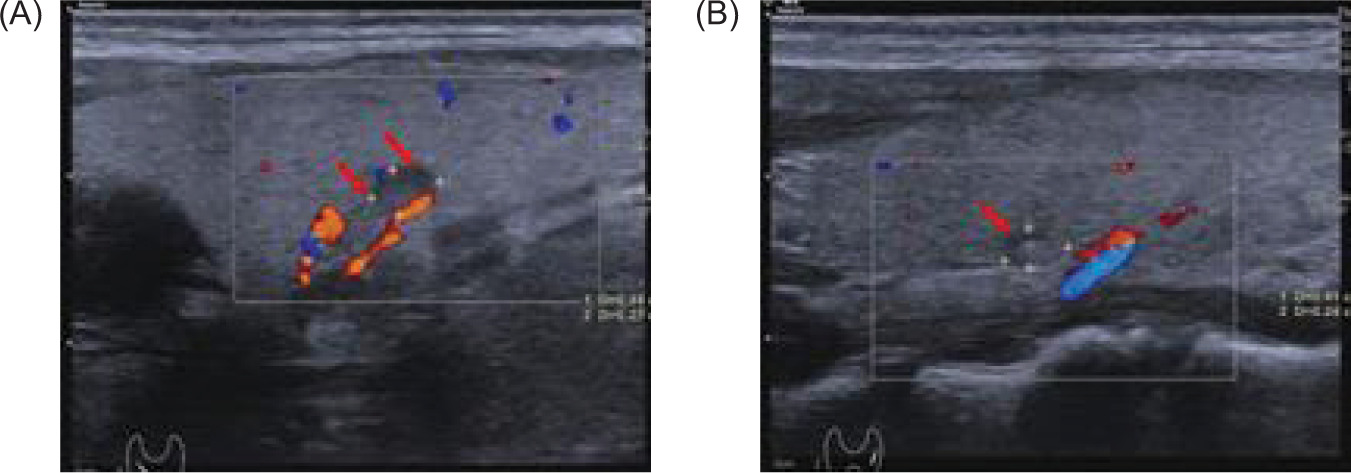

Brain MRI revealed a cystic mass in the right cerebellar hemisphere measuring approximately 40 mm (Figure 6). Thyroid color Doppler ultrasound revealed solid and cystic nodules in both thyroid lobes (C-TIRADS: Category 3) (Figure 7). His fasting blood glucose level was 20.6 mmol/L. On November 29, 2024, he was treated with intensive insulin therapy, and his antidiabetic regimen was adjusted to injection aspart insulin, 4 units tds daily before meals and injection degludec insulin, 5 units once daily at night. The patient’s fasting blood glucose stabilized at 4.5–5.0 mmol/L, and postprandial blood glucose stabilized at 6.0–8.0 mmol/L in 3 days before discharge, and his clinical manifestations, such as polydipsia and weakness in the lower limbs, decreased significantly.

Figure 7: Thyroid color Doppler ultrasound shows bilateral cystic and solid thyroid nodules with clear boundaries, measuring (A) about 0.44×0.27 cm (right) (red arrow), and (B) 0.41×0.24 cm (left) (red arrow) (C-TIRADS: category 3).